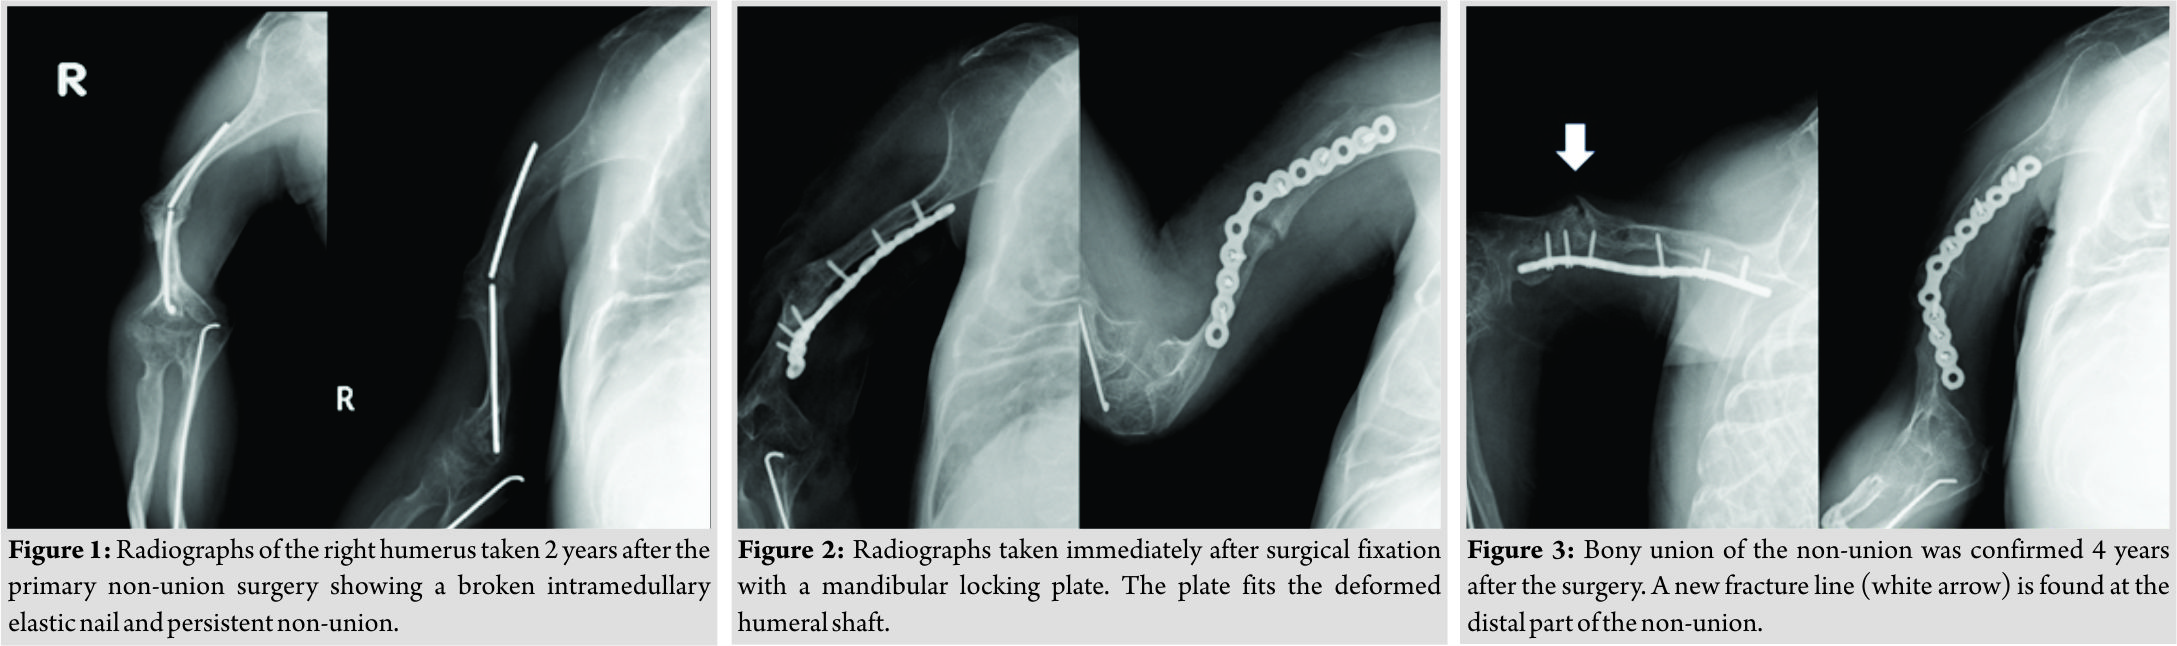

A 26-year-old man with Type III OI and a history of correction osteotomy and intramedullary Kirschner wire fixation in his right humerus at the age of 8 years felt gradually increasing pain in his humerus. His left upper limb and both lower limbs were not functional, and he lived in an electric wheelchair. He was unable to manually operate the wheelchair and instead moved it with a switch using his right hand. His right upper limb was his only functional extremity. He had developed humeral shaft non-union due to a broken Kirschner wire used in the previous operation. He was referred to our hospital and underwent internal fixation using an intramedullary elastic nail with an autogenous iliac bone graft. However, 2 years after the operation, bony union was not achieved and elastic nail breakage had occurred, and he complained of pain and limitation of activity (Fig. 1). He underwent a re-operation for his humeral non-union using a locking plate to achieve rigid fixation. Since his humeral shaft was extremely narrow with severe deformity, we used a locking plate for the mandibular bone, which was contoured to fit the medial side of the humeral shaft (Fig. 2). Bony union was achieved, and he became free from pain and returned to his pre-injury activity with no symptoms. No implant failure or refracture of his humeral shaft had occurred 4 years later, but a new fracture line was found in radiographs of the distal part of the non-union (Fig. 3). We used a cast to fix the new fracture for 9 weeks and then a splint for 4 weeks.He recovered well, and at the time of this writing, he was maintaining normal function of the right upper limb and was able to perform activities of daily life without problems.

Type III OI causes severe bone fragility, and multiple fractures are usually present at birth. These patients develop a severely shortened height and progressive deformity of the limbs and spine with age. Due to their poor bone quality, patients with OI are prone to fractures. These fractures are often difficult to manage because their narrow bone shafts provide limited surface area for contact of prostheses and because bowing adds mechanical stress. In addition, poor bone quality disturbs most treatment plans, especially surgical treatment. Although most low-energy fractures in patients with OI may heal uneventfully, some will fail to achieve bony union. Non-union is more common in patients with than without OI, and patients with Sillence Type III OI are at particularly high risk of non-union. Studies have estimated that approximately 20% of patients with OI develop non-union [4, 5, 6]. In one study, the rate of non-union was slightly lower in patients treated surgically than in those treated conservatively, but the difference was not statistically significant [7]. To obtain good bone fusion, fixation with intramedullary elastic nailing should be considered for femoral non-union complicated by OI [8]. The use of sandwich allograft struts is a durable, safe method for the stabilization and healing of persistent long bone non-union in patients with OI [9]. Intramedullary fixation with autogenous bone graft, combined with concomitant realignment if necessary, is the first-choice treatment for non-union without significant segmental bone loss. Similarly, shortening with an autogenous bone graft and intramedullary fixation is suggested for small gap non-union [10]. In the present case, we selected a locking plate for treatment due to the short diameter of the medullary cavity in the humeral shaft, the hard deformation, the hypertrophic non-union, and the poor bone quality. We used a matrixmandible reconstruction plate “DePuy Synthes, West Chester, PA, USA”. This plate was easy to bend and could be adapted to this case. In addition, this plate was suitable for the patient’s short bone transverse diameter because the screw diameter was also small. The patient’s humeral deformation was hardly a hindrance in his daily life before the development of the non-union. We attempted to fix the bone with a locking plate without correction osteotomy. Hanke et al. [11] reported that the locking plate technique was successful as a salvage procedure in a rare case of adult OI presenting with a femoral fracture. The advantage of using a locking plate is that screws with angular stability are evenly distributed throughout the load without concentrating at one contact point between the bone and the screw. If the fixing force of a conventional plate is lost, it usually starts with a single screw and spreads from there to other screws. The same phenomenon does not occur in a locking screw. Compared with conventional plate constructs, locking plates have mechanical advantages and are thus useful in patients with osteoporosis [12, 13]. Although the current patient was young, his condition was accompanied by bone fragility; locking plates are also useful in such cases. An asymptomatic slight fracture line developed during the 4 years follow-up period. No deterioration was observed by careful follow-up, and the patient attained a partial cure. Although fixation breakdown did not occur, slight screw loosening was observed on X-ray examination. This was not a problem at the time of the present writing, but careful follow-up is necessary.